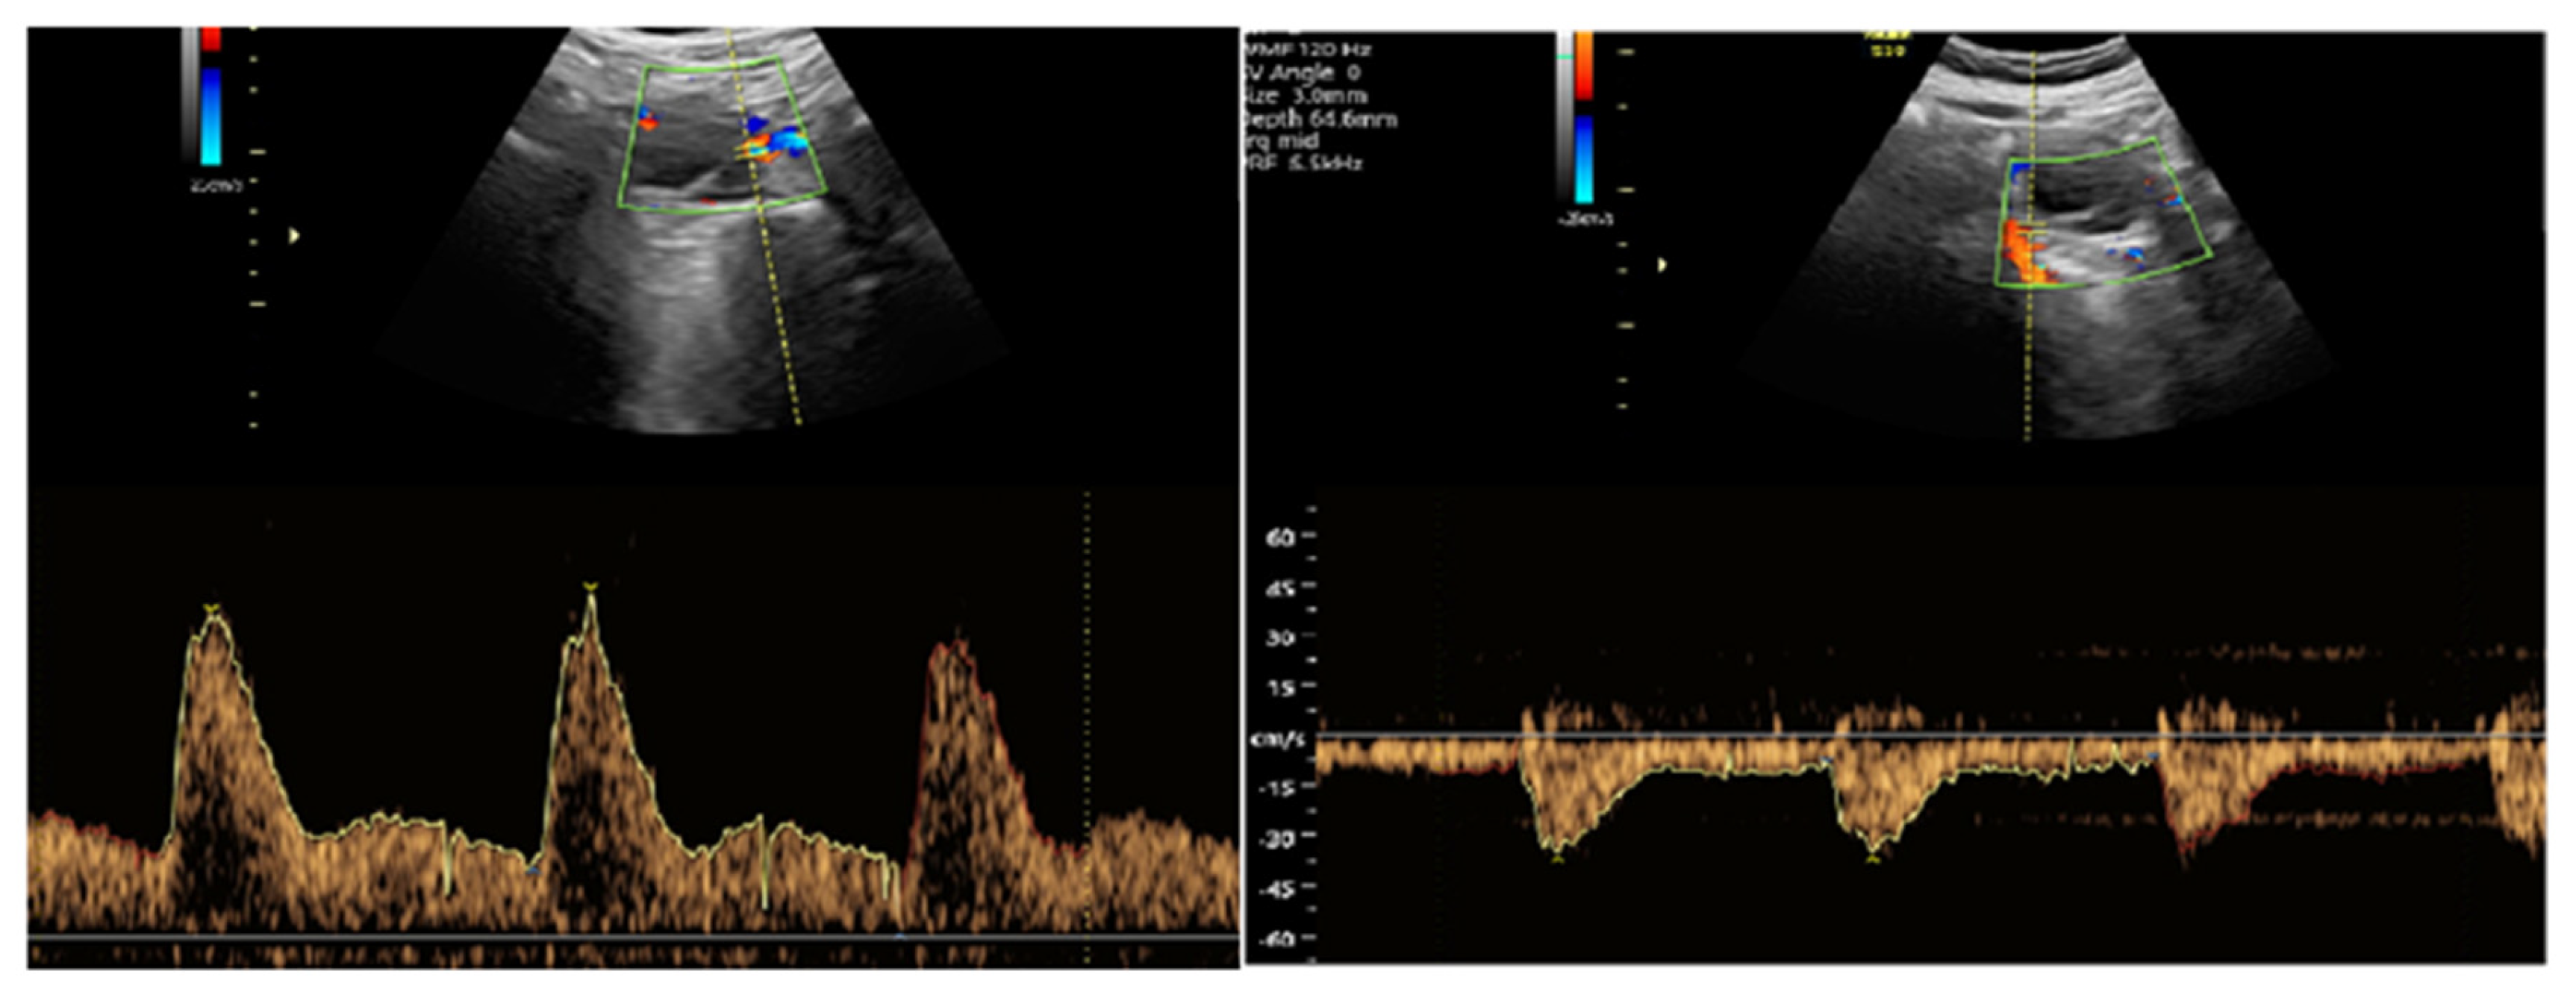

2.3.2. Doppler Measurement Procedure

- S/D ratio (Systolic/Diastolic ratio)

- RI (Resistance Index)

- PI (Pulsatility Index)